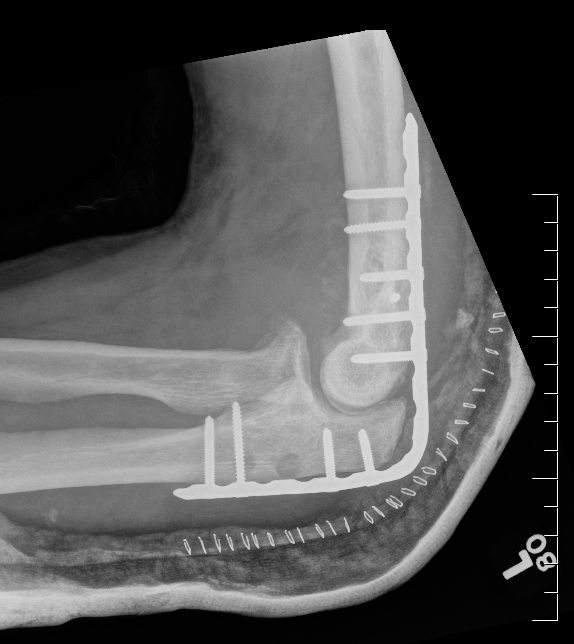

Internal fixation with posterior plating

Surgical technique